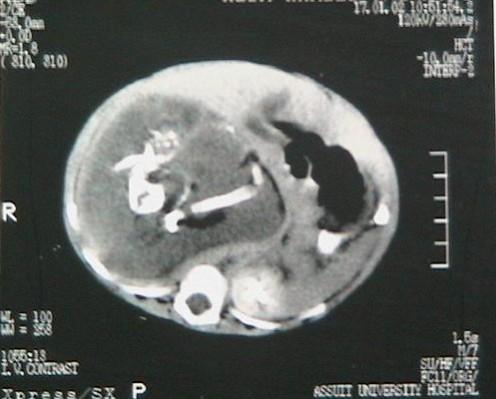

The parents, who were extremely worried, took Prinsa to a hospital where a 130g fetus was found between the intestines and kidneys of the little girl.

Dr. Joshi said: "There will be no future complications in the case and she will grow up normally. The surgery was tough as the undeveloped fetus was behind the intestine and between both the kidneys."